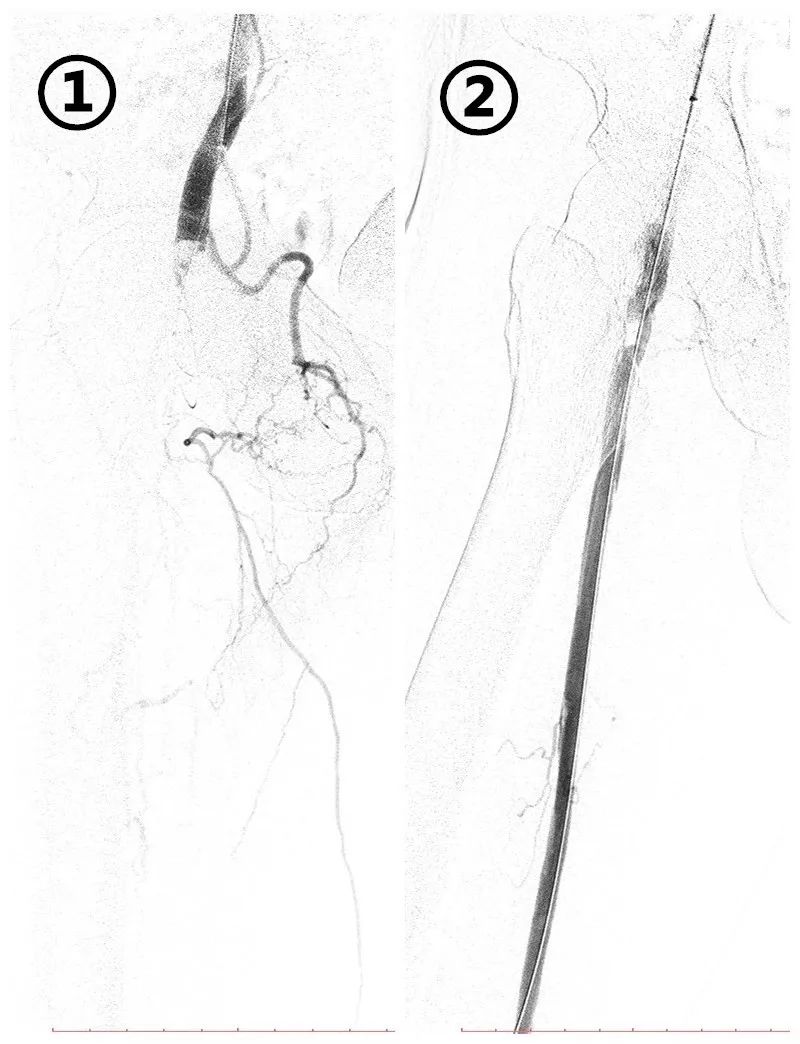

①吸栓前右股浅动脉全程栓塞;

②吸栓后右股浅动脉复通